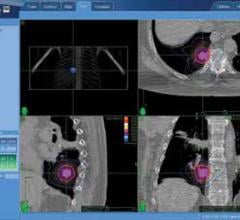

The nonprofit healthcare provider Swedish Medical Center (SMC) has been serving the Seattle area for more than 100 years. It has locations in both the city of Seattle and its surrounding suburbs, providing care in specialty areas such as cardiology, neuroscience, orthopedics, pediatrics and more. An integral part of the community, Swedish is unique in that it offers both technologies from Accuray, the TomoTherapy System and the CyberKnife System, for treating cancer patients in the metropolitan region.

Erlanger Health System in Chattanooga, Tennessee, purchased a CyberKnife Robotic Radiosurgery System in December 2010 to develop a stereotactic body radiation therapy (SBRT) program in its Radiation Oncology Department. The CyberKnife System included the Lung Optimized Treatment (LOT) function, which provides fiducial-free SBRT of early-stage lung cancer patients by enabling a hybrid method of spine tracking and tumor density tracking. Once the CyberKnife System was in use, the clinical team at Erlanger collaborated with referring physicians to explain to thoracic surgeons and pulmonologists — at Erlanger and other hospitals in the community — how the system could be utilized as a treatment option for their patients.

UT Southwestern Medical Center Kidney Cancer Program investigators have published what is believed to be the first reported successful use of stereotactic body radiation therapy for an often-deadly complication of kidney cancer.